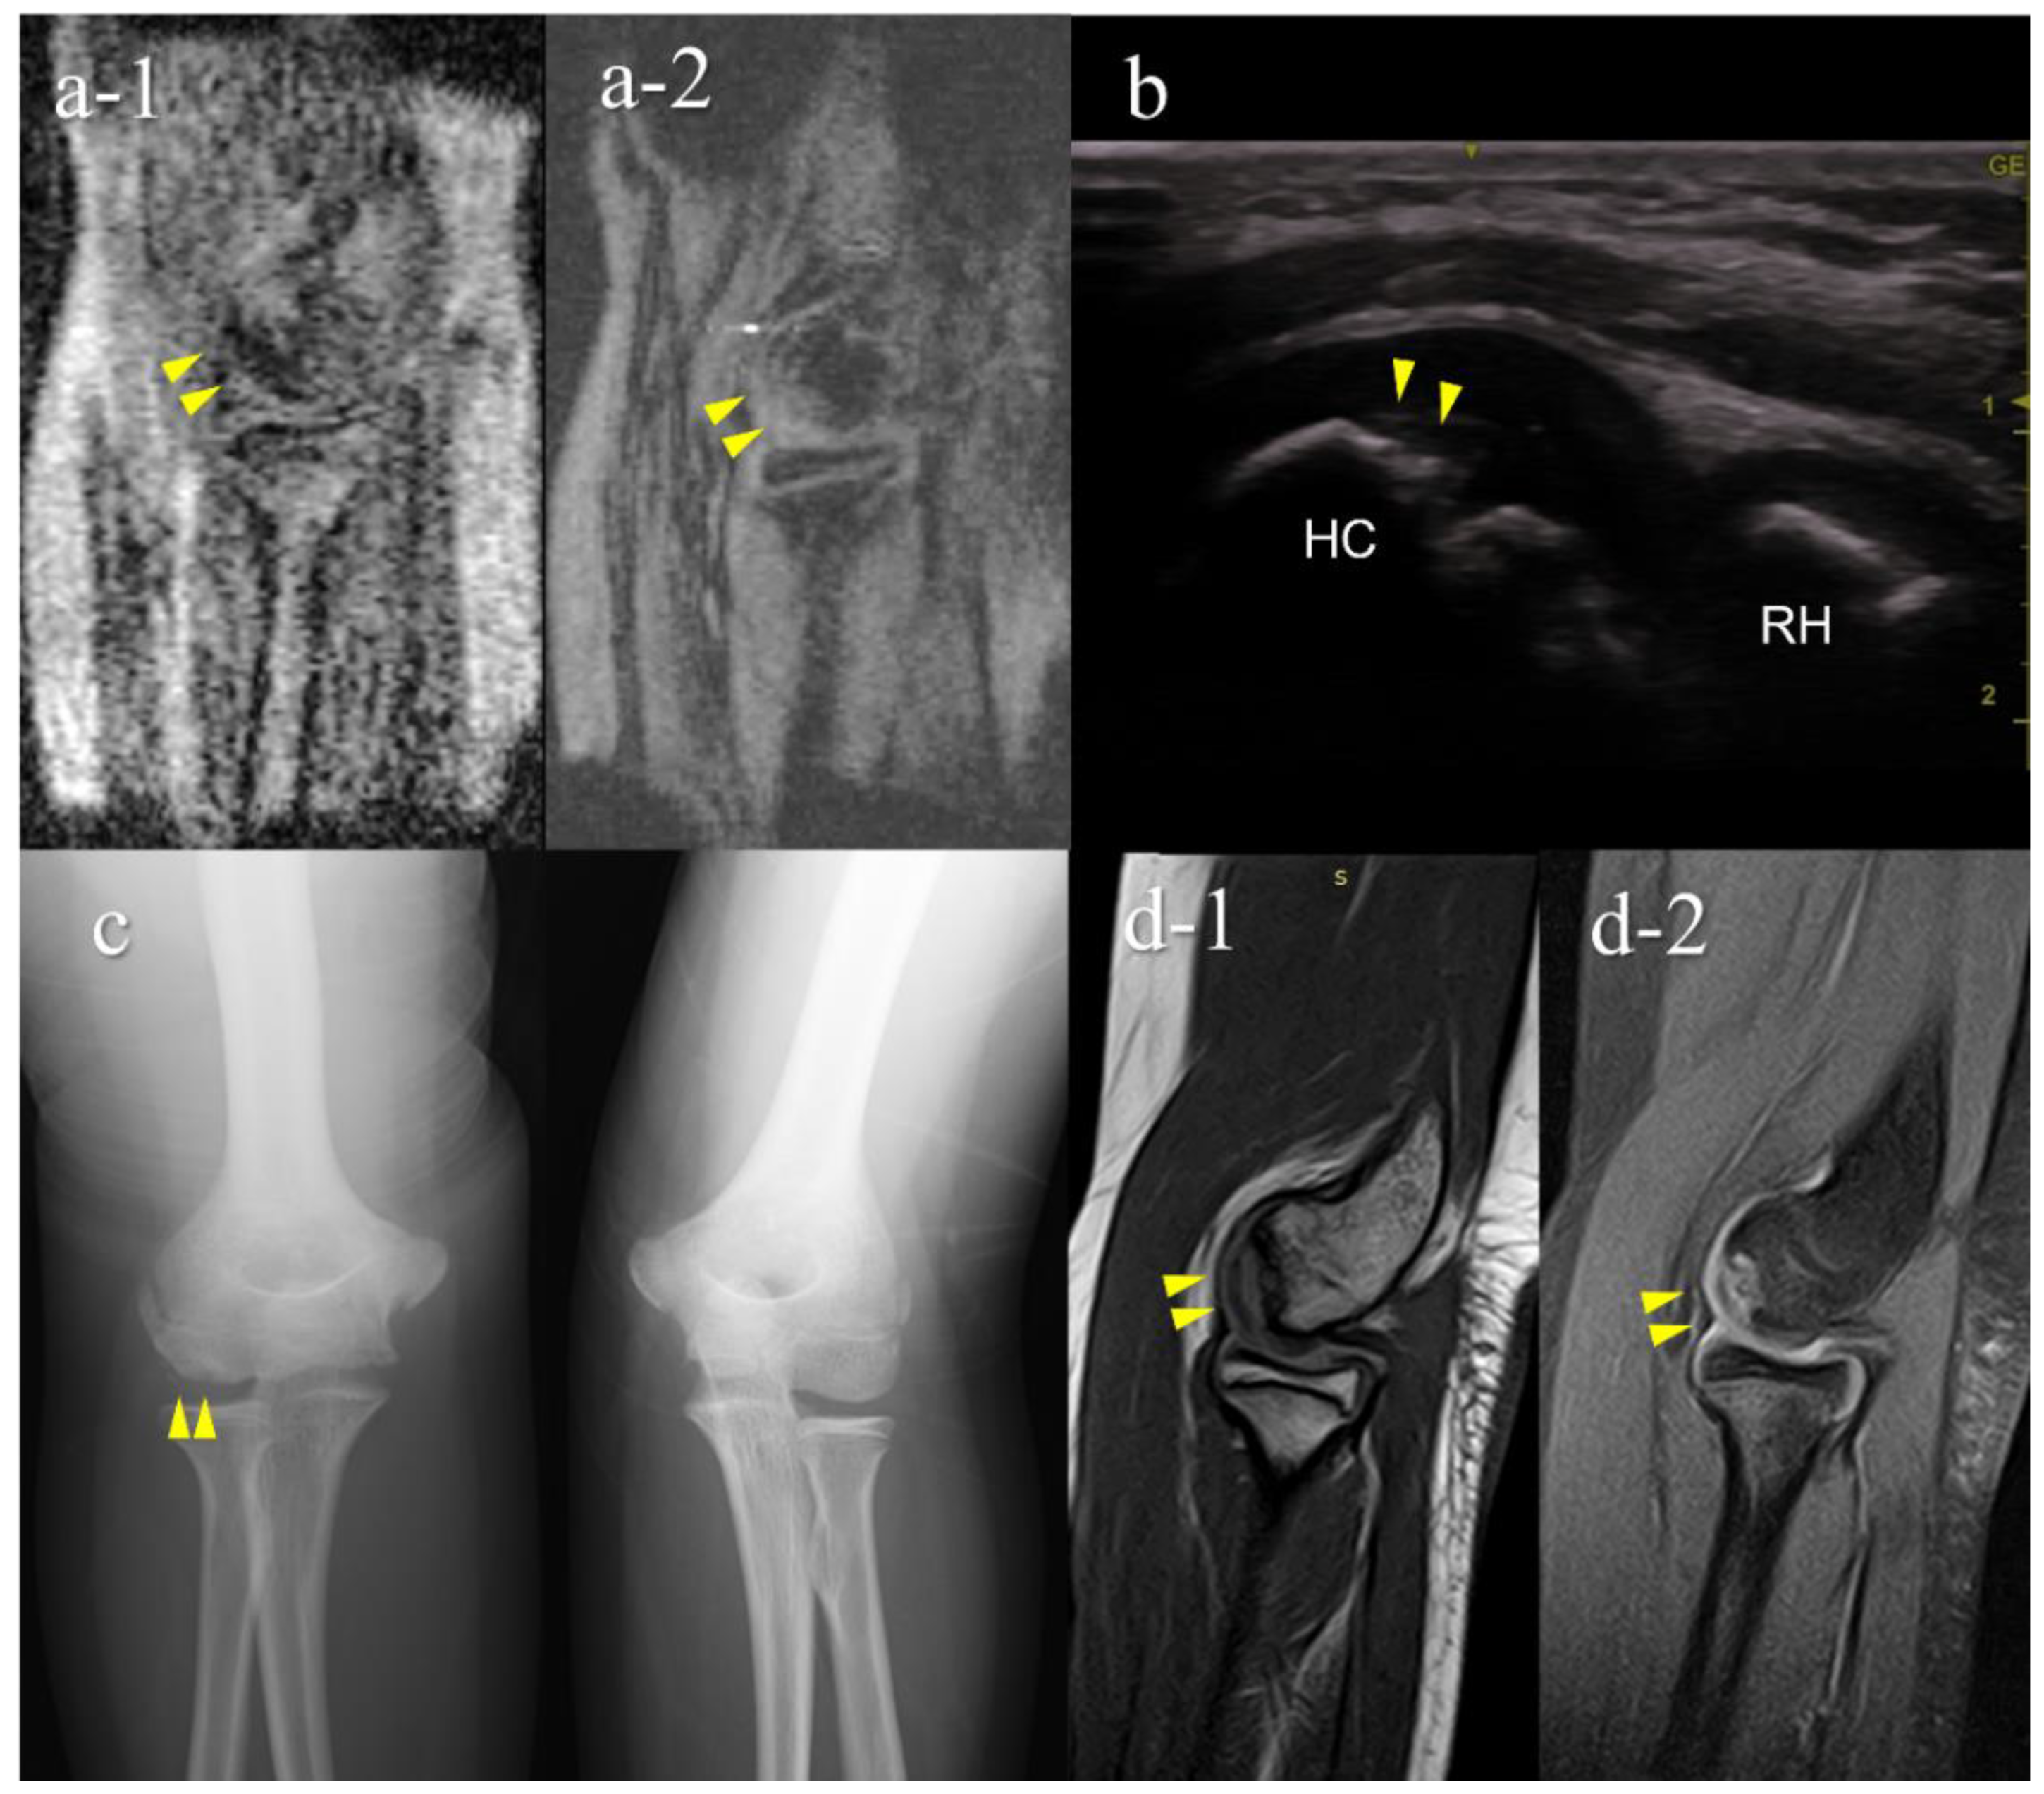

| 1 | 12 | M | - | − (1st) | + (B) | OCD | II | lateral | 15 |

| 2 | 11 | M | + | + (1st) | + (B) | OCD | I | central | 10 |

| 3 | 12 | M | - | + (2nd) | + (B) | OCD | II | central | 9 |

| 4 | 12 | M | + | + (2nd) | + (B) | OCD | II | lateral | 11 |

| 5 | 12 | M | + | + (2nd) | − (B) | OCD | I | central | 3.5 |

| 6 | 15 | F | - | + (2nd) | − (C) | not OCD | posterior | 3.5 | |

| 7 | 12 | M | - | + (2nd) | − (D) | OCD | I | central | 5.5 |